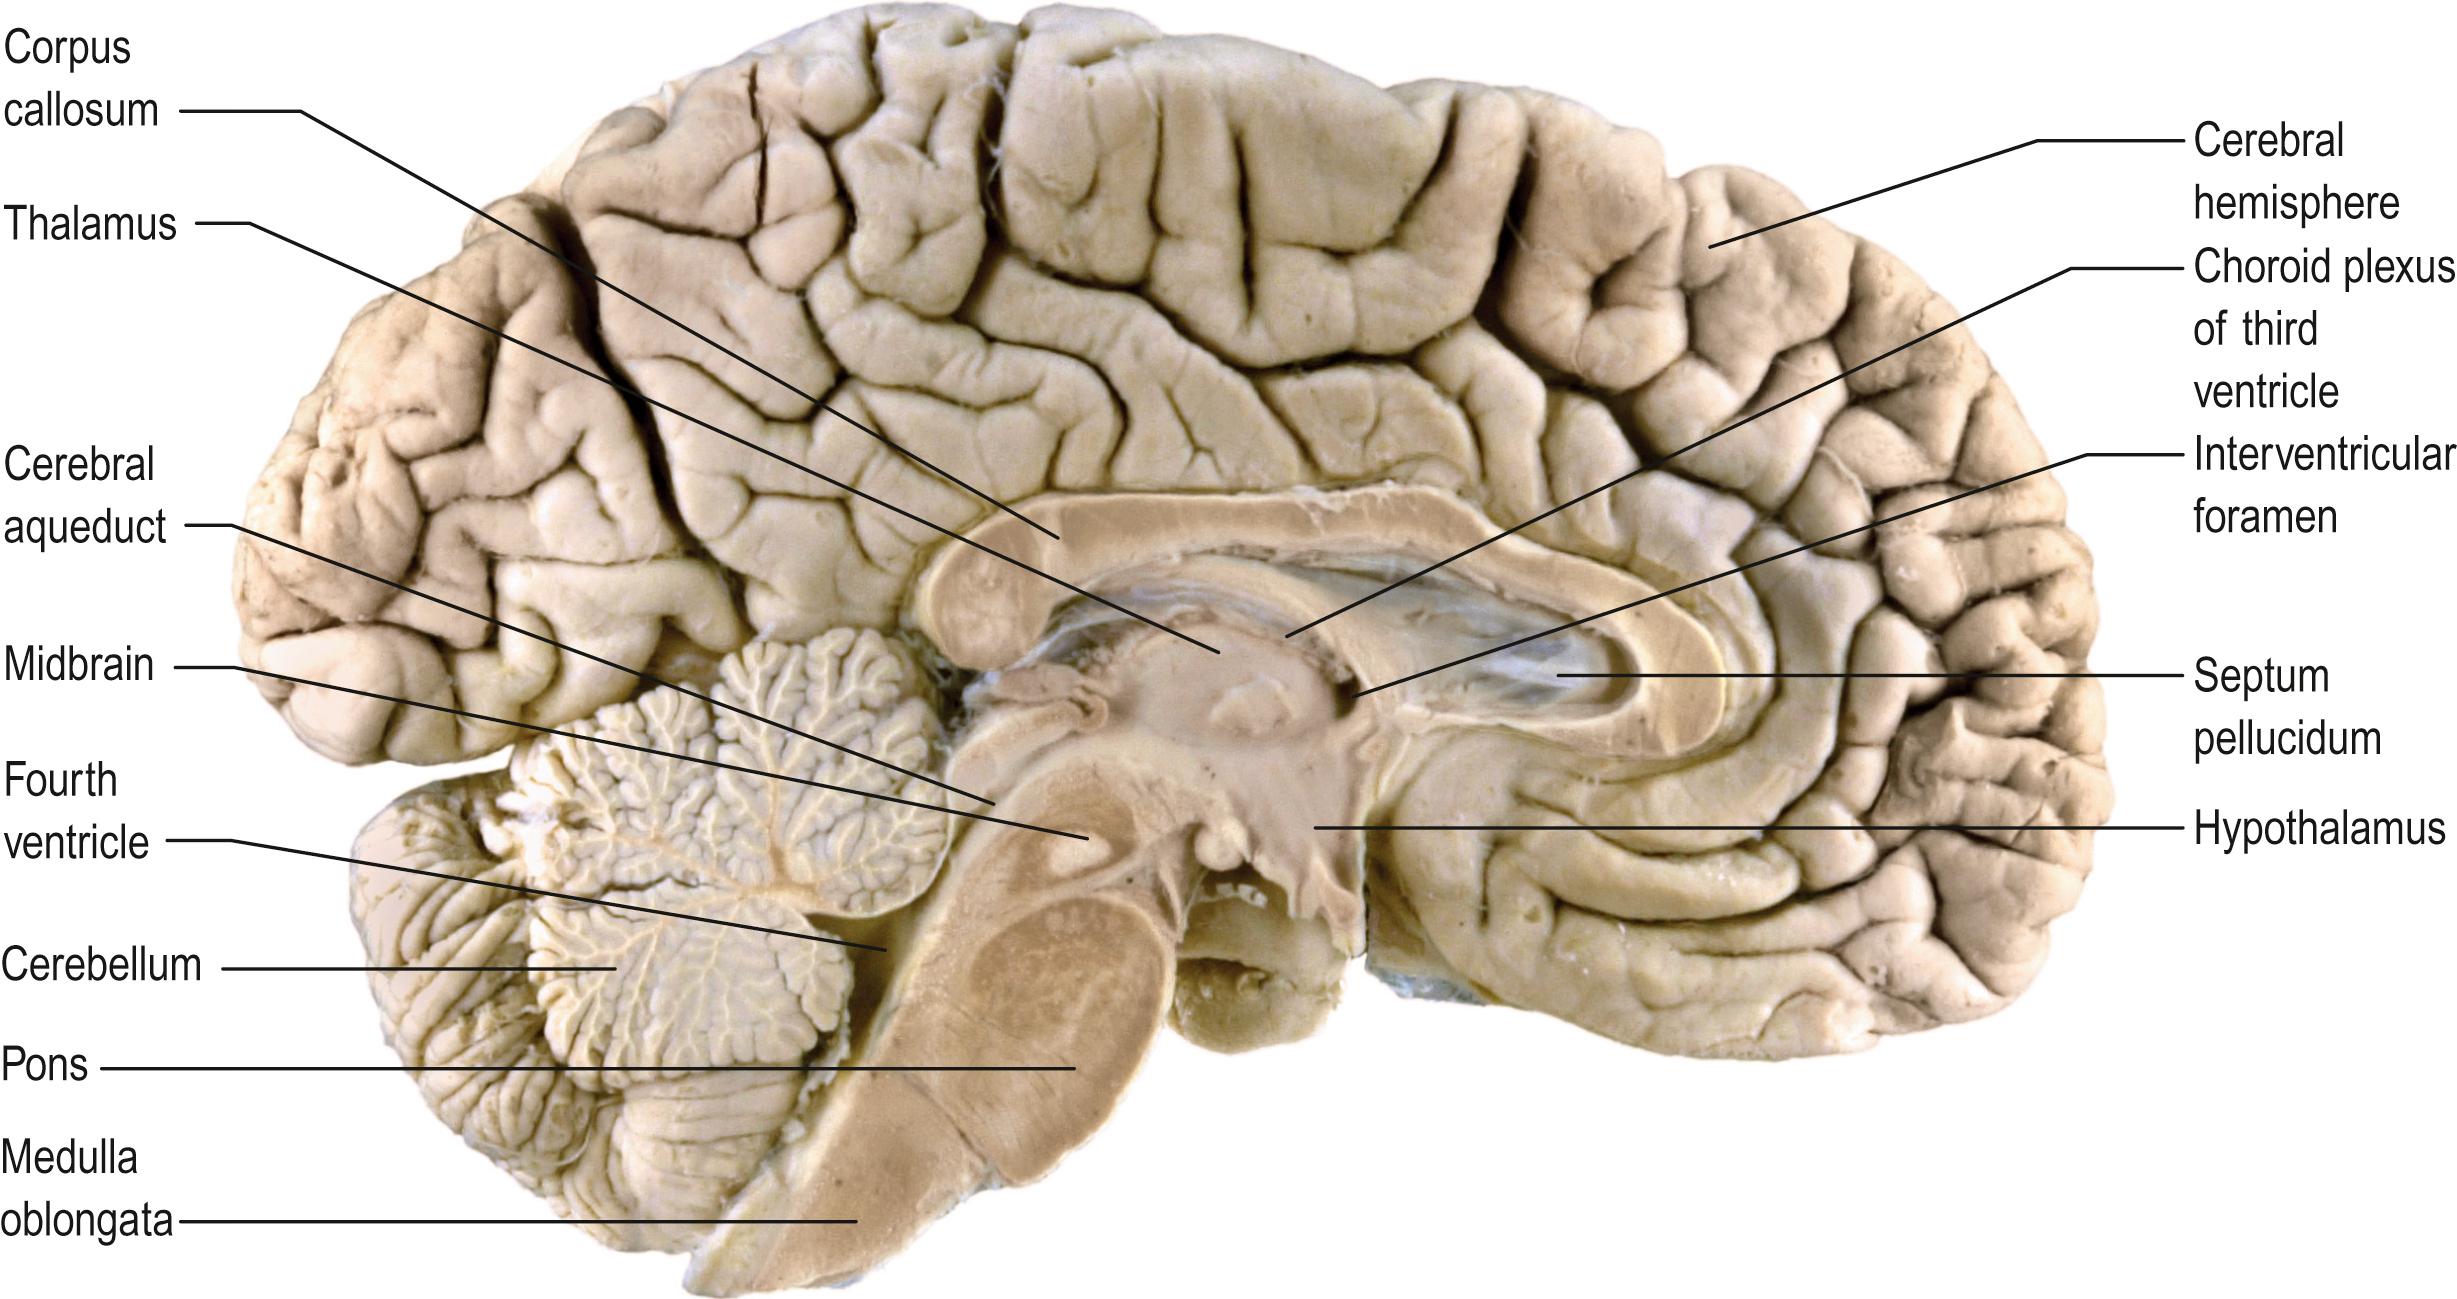

The brain and spinal cord (see Fig. 47.1A ) contain the great majority of neuronal cell bodies in the nervous system. In many parts of the CNS, neuronal cell bodies are grouped together and are, more or less, segregated from axons. The generic term for such collections of cell bodies is grey matter. Small aggregations of neuronal cell bodies, which usually share common connections and functional roles, are termed nuclei. Neuronal dendrites and synaptic interactions are mostly confined to grey matter. Axons tend to be grouped together to form white matter, so named because axons are often ensheathed in myelin, which confers a paler coloration on the tissue. Axons that pass between similar origins or destinations within the CNS tend to run together in defined pathways, or tracts. These often cross the midline (decussate), which means that one half of the body is, in many respects, controlled by, and sends information to, the opposite side of the brain.

Internally, the spinal cord consists of a central core of grey matter surrounded by white matter. The grey matter is configured in a characteristic H, or butterfly, shape that has projections known as dorsal (posterior) and ventral (anterior) horns ( Fig. 24.3 ). In general, neurones situated in the dorsal horn are primarily concerned with sensory functions whilst those in the ventral horn are mostly associated with motor activities. At thoracic and upper lumbar levels of the spinal cord a small lateral horn is additionally present, marking the location of the cell bodies of preganglionic sympathetic neurones. The central canal, a vestigial component of the ventricular system, lies at the centre of the spinal grey matter and runs the length of the cord. The white matter of the spinal cord consists of ascending and descending tracts that link spinal cord segments to one another and the spinal cord to the brain.

Fig. 24.6, A sagittal section of the brain.

The rhombencephalon is subdivided into the myelencephalon or medulla oblongata, metencephalon or pons, and the cerebellum. The medulla oblongata, pons and midbrain are collectively referred to as the brainstem: it lies upon the basal portions of the occipital and sphenoid bones (clivus). The medulla oblongata is the most caudal part of the brainstem and is continuous with the spinal cord below the level of the foramen magnum. The pons lies rostral to the medulla and is distinguished by a mass of transverse nerve fibres that connect it to the cerebellum. The midbrain is a short segment of brainstem, rostral to the pons. The cerebellum consists of paired hemispheres united by a median vermis: it lies within the posterior cranial fossa, dorsal to the pons, medulla and caudal midbrain, with all of which it has numerous fibre connections.

The prosencephalon is subdivided into the diencephalon and the telencephalon. The diencephalon equates mostly to the thalamus and hypothalamus, but also includes the smaller epithalamus and subthalamus. The telencephalon is composed mainly of the cerebral hemisphere or cerebrum. The diencephalon is almost completely embedded in the cerebrum and is, therefore, largely hidden from the exterior. The human cerebrum constitutes the major part of the brain. It occupies the anterior and middle cranial fossae and is directly related to the calvaria. The surface of the cerebral hemisphere is convoluted into a complex pattern of ridges (gyri) and furrows (sulci). Internally, the hemisphere has an outer layer of grey matter, the cerebral cortex, beneath which lies a thick mass of white matter ( Fig. 24.7 ). One of the most important components of the cerebral white matter, the internal capsule (see Fig. 24.9 ), contains nerve fibres that pass to and from the cerebral cortex and lower levels of the neuraxis. Several large nuclei of grey matter, the basal ganglia or basal nuclei, are partly embedded in the subcortical white matter. Nerve fibre connections between corresponding areas on either side of the brain cross the midline within commissures, the largest being the corpus callosum.

During prenatal development, the walls of the neural tube thicken greatly but never completely obliterate the central lumen, which remains in the spinal cord as the vestigial central canal and becomes greatly expanded in the brain to form a series of interconnected cavities or ventricles ( Ch. 25 ). In the forebrain and hindbrain, parts of the roof of the neural tube do not generate nerve cells but become thin, folded sheets of highly vascular secretory tissue, the choroid plexuses which secrete cerebrospinal fluid into the ventricles. The cavity of the rhombencephalon becomes expanded to form the fourth ventricle dorsal to the pons and upper half of the medulla. Caudally, the fourth ventricle is continuous with a canal in the caudal medulla and, through this, with the central canal of the spinal cord. It is continuous with the subarachnoid space through three openings (the foramina of Luschka and of Magendie) and with a narrow channel, the cerebral aqueduct, at its rostral extent. The cerebral aqueduct passes through the midbrain and opens out rostrally into the third ventricle, a narrow, slit-like, midline cavity bounded laterally by the diencephalon. At the rostral end of the third ventricle, a small aperture on each side leads into the large lateral ventricle located within each cerebral hemisphere (see Fig. 24.4C ).